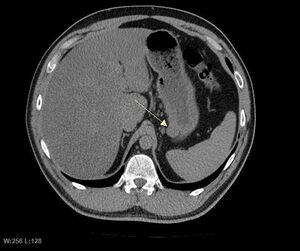

لتشخيص الأورام السدية المعدية المعوية غالباً ما يُجرى التصوير المقطعي المحوسب (انظر قسم علم الأشعة). إن الصبغة الكيميائية النسيجية المناعية للبيتا-كاتينين في نوى الخلايا هو نتيجة ثابتة في الأورام الليفية الرحمية، ويساعد في التمييز بين مثل هذه الأورام وأورام الخلايا المغزلية الموجبة للبيتا كاتينين.[18]

التصوير الطبي

الغرض من التصوير الإشعاعي هو تحديد موقع الآفة، وتقييم علامات الغزو، والكشف عن النقائل. تختلف سمات الأورام السدية المعدية المعوية باختلاف حجم الورم والعضو المنشأ. يمكن أن يتراوح قطرها من بضعة مليمترات إلى أكثر من 30 سم. عادةً ما تُسبب الأورام الأكبر أعراضاً، على عكس تلك التي تُكتشف بالصدفة، والتي عادةً ما تكون أصغر حجماً وذات تشخيص أفضل.[4][20] تميل الأورام الكبيرة إلى إظهار سلوك خبيث لكن الأورام السدية المعدية المعوية الصغيرة قد تظهر أيضاً سلوكاً عدوانياً سريرياً.[21]

تُستخدم فحوصات الباريوم الفلوري والتصوير المقطعي المحوسب عادةً لتقييم المرضى الذين يعانون من مشاكل في البطن. تُظهر صور الباريوم الفلوري وجود تشوهات في 80% من حالات الأورام السدية المعدية المعوية.[21] مع ذلك، قد تحدث بعض الأورام السدية المعدية المعوية خارج تجويف الأمعاء تماماً، ولا يُمكن تشخيصها بفحص الباريوم. حتى في الحالات التي يكون فيها فحص الباريوم غير طبيعي، يجب إجراء تصوير بالرنين المغناطيسي أو التصوير المقطعي المحوسب، إذ يستحيل تقييم تجاويف البطن وأعضاء البطن الأخرى بفحص الباريوم وحده. في التصوير المقطعي المحوسب، قد تُلاحظ تشوهات لدى 87% من المرضى، ويجب إجراؤه باستخدام مادة تباين فموية وريدية.[21] من بين دراسات التصوير، يُعدّ التصوير بالرنين المغناطيسي أفضل تباين للأنسجة، مما يُساعد في تحديد الكتل داخل الجهاز الهضمي (الكتل داخل الجدار). يلزم حقن مادة تباين وريدية لتقييم الأوعية الدموية في الآفة.

طرق التصوير المفضلة في تقييم الأورام السدية المعدية المعوية هي التصوير المقطعي المحوسب والتصوير بالرنين المغناطيسي،[23] وفي حالات معينة، الموجات فوق الصوتية بالمنظار. تشمل مزايا التصوير المقطعي المحوسب قدرته على إظهار أدلة على غزو الأعضاء المجاورة، والاستسقاء، والنقائل. كما أن قدرة التصوير بالرنين المغناطيسي على إنتاج صور في مستويات متعددة تُساعد في تحديد الأمعاء كعضو منشأ (وهو أمر صعب عندما يكون الورم كبيراً جداً)، مما يُسهّل التشخيص.

بما أن الأورام السدية المعدية المعوية تنشأ من طبقة الأمعاء المسماة بالطبقة العضلية (وهي أعمق من الغشاء المخاطي وتحت المخاطي من منظور التجويف)، فإن تصوير الأورام السدية المعدية المعوية الصغيرة عادةً ما يشير إلى نتوء تحت مخاطي أو كتلة داخل جدار الأمعاء. في دراسات تصوير الجهاز الهضمي بالباريوم، تظهر الأورام السدية المعدية المعوية الصغيرة هذه عادةً بحواف ناعمة تُشكل زوايا قائمة أو منفرجة مع جدار الأمعاء القريب، كما هو الحال مع أي كتلة داخلية أخرى. عادةً ما يكون السطح المخاطي سليماً باستثناء مناطق التقرح، والتي توجد عادةً في 50% من الأورام السدية المعدية المعوية. تمتلئ التقرحات بالباريوم مما يتسبب في ظهور عين الثور أو الآفة المستهدفة. في التصوير الطبقي المحوسب المعزز بالتباين، تُرى الأورام السدية المعدية المعوية الصغيرة على شكل كتل داخلية ناعمة ومحددة بوضوح مع توهين متجانس.

مع نمو الورم، قد يبرز خارج الأمعاء (نمو خارجي) و/أو داخلها (نمو داخل التجويف)، لكن في أغلب الأحيان ينمو الورم خارجياً بحيث يبرز الجزء الأكبر منه في تجويف البطن. إذا تجاوز الورم إمداده الدموي، فقد ينخر داخلياً، مكوّناً تجويفاً مركزياً مملوءاً بالسوائل مع نزيف وتجويفات قد تتقرح في النهاية وتتصل بتجويف الأمعاء. في هذه الحالة، قد يُظهر فحص الباريوم وجود هواء، أو مستويات هواء-سوائل، أو تراكماً لوسائط التباين الفموية في هذه المناطق.[21][25] قد تظهر أيضاً تقرحات مخاطية. في صور الأشعة المقطعية المحسنة بالتباين، تظهر أورام الجهاز الهضمي المعدية الكبيرة ككتل غير متجانسة بسبب وجود مناطق من خلايا الورم الحية المحيطة بالنزيف أو النخر أو الأكياس، والتي تُرى شعاعيًا كنمط تعزيز محيطي بمركز توهين منخفض.[20] في دراسات التصوير بالرنين المغناطيسي، تؤثر درجة النخر والنزيف على نمط شدة الإشارة. تختلف شدة الإشارة في مناطق النزيف داخل الورم تبعًا لتاريخ حدوث النزيف. عادةً ما تكون شدة الإشارة في الأجزاء الصلبة من الورم منخفضة في صور الرنين المغناطيسي الموزونة بـ T1، وتكون شدة الإشارة فيها عالية في صور الرنين المغناطيسي الموزونة بـ T2، وتزداد بعد إعطاء الگادولينيوم. توجد فراغات ذات شدة إشارة في حال وجود غاز داخل مناطق الورم النخرية.[22][26][27]

تتميز الأورام الخبيثة بالغزو الموضعي والانتشار، عادةً إلى الكبد، والثرب، والصفاق. ومع ذلك، فقد لوحظت حالات انتشار الورم إلى العظام، والتجويف الجنبي، والرئتين، وخلف الصفاق. بخلاف السرطانة الغدية المعدية أو سرطان الغدد اللمفاوية في المعدة/الأمعاء الدقيقة، فإن تضخم العقد الليمفاوية الخبيث نادر (<10%)، وبالتالي يُظهر التصوير عادة غياب تضخم العقد الليمفاوية.[20] إذا لم تكن النقائل موجودة، فإن السمات الشعاعية الأخرى التي تشير إلى الخباثة تشمل: الحجم (>5 سم)، والتعزيز غير المتجانس بعد إعطاء التباين، والتقرحات.[4][20][28] كما أن السلوك الخبيث الواضح (على النقيض من احتمالية الخباثة بدرجة أقل) أقل شيوعاً في أورام المعدة، حيث تبلغ نسبة من السلوك الحميد إلى السلوك الخبيث الواضح تتراوح بين 3-5.[4] حتى لو كانت السمات الخبيثة الشعاعية موجودة، فإن هذه النتائج قد تمثل أيضاً أوراماً أخرى ويجب إجراء التشخيص النهائي كيميائياً مناعياً.